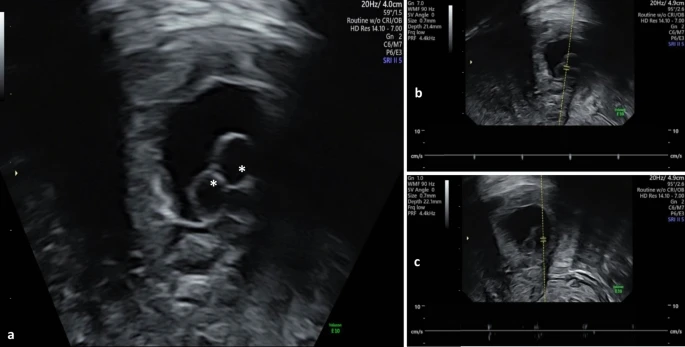

She was hemodynamically stable, and the physical examination was unremarkable. Transvaginal ultrasound revealed an empty uterine cavity. And an eccentric gestational sac on the right side of the uterine fundus, contained within the uterine serosa. But a thin band of myometrium separated the uterine serosa from endometrial cavity. The gestational sac measurements were consistent with the last menstrual cycle. It consisted of two yolk sacs and two embryonic poles with cardiac activity with no amniotic membrane. These ultrasonographic findings suggested a twin right interstitial pregnancy.

In this case, a single gestational sac containing two yolk sacs and two embryonic poles with cardiac activity indicated a monochorionic twin pregnancy. Although the quantity of yolk sacs is occasionally used to predict amnioticity in early gestation, it is not always reliable. Furthermore, the absence of a visible amniotic membrane at this stage does not rule out diamnioticity, as sonographic detection may be delayed. As a result, while monochorionicity has been verified, amnionicity remains undetermined.

Interstitial pregnancy diagnostic criteria via ultrasound include: (1) gestational sac located outside the uterine cavity, (2)partial surrounding of the sac by myometrium, and (3) visualization of the interstitial line sign. That shows an intramural segment of the Fallopian tube next to the gestational sac and uterine cavity.